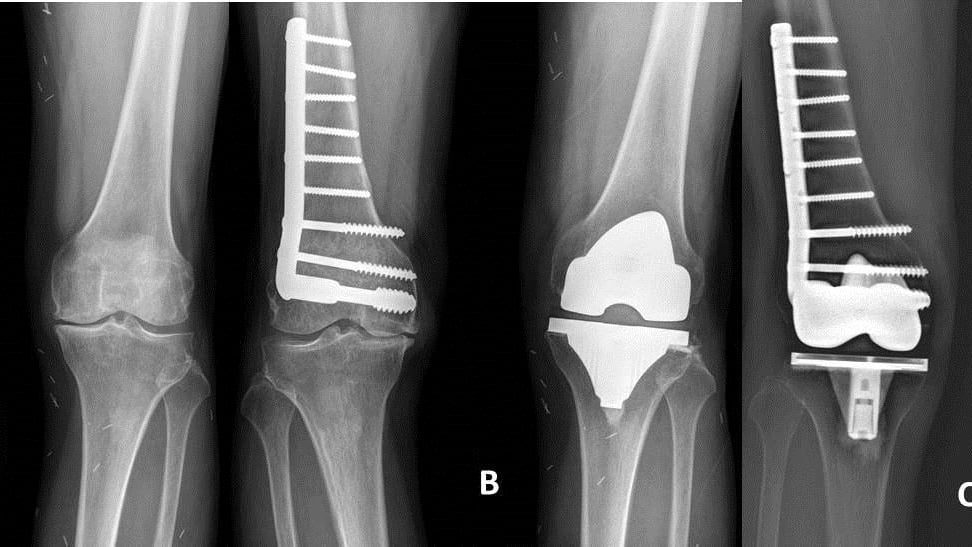

1年後,許先生右膝的疼痛失能到無法以藥物控制,想以手術治療,但因年輕時曾因大腿骨折接受復位固定,當時遠端股骨植入物迄今未拆,若要以現今常用手術器械進行關節置換,可能得先拆除原來相處數十載的骨板骨釘,增加手術時間與失血,另外還得以較複雜設計的關節組件植入,以避免周邊骨折的風險。張志偉醫師表示,後來以成大醫院關節重建團隊近10年所發展出的保留髓腔人工膝關節置換技術,不但保留了先前的骨折固定物,且在未增加手術時間下,成功地以較簡單的初次關節置換組件進行手術,術後恢復良好。

張志偉醫師指出,全膝關節置換手術對創傷後膝關節炎是一種有效的手術治療;但在醫學文獻中,此類手術相較於一般單純因退化接受關節置換手術者,有較多感染、僵硬和傷口癒合的併發症。且原本因治療創傷骨折或韌帶重建的植入物,往往會阻礙現今關節置換手術慣用髓內導引方式骨髓腔內定位桿的放置,所以大多數醫師習慣在關節置換前,分階段或手術同時,先移除這些植入物;但如此一來,不但增加手術時間、耗用更多健保資源外,也因較多較大的傷口增加失血量,延遲病患術後復原,甚至感染風險。

而這種應用簡單平行律的保留髓腔人工膝關節置換技術,不但可有效解決患者因創傷性關節炎造成的行走不便,也避免因拆除先前植入物產生的手術創傷與相關風險!